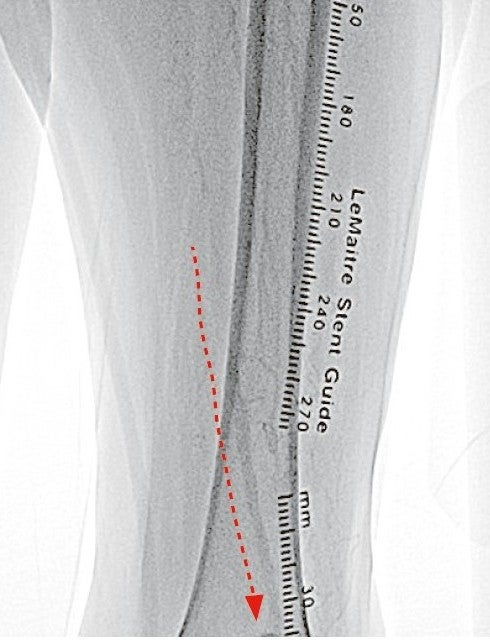

右大腿動脈穿刺、0.035 inchワイヤーを用いて、ガイディングシース 6 Fr 60 cmを左外腸骨動脈まで誘導し、造影を行った(図1.2)。体表面エコーガイドのもと、マイクロカテーテルと0.014 inch フロッピー300 cmワイヤーで、確実に浅大腿動脈入口部から血管真腔内を進めた。0.014 inch フロッピー300 cmワイヤーを抜去し、血管狭窄部貫通用カテーテルに交換し、閉塞部位を慎重に進め、貫通に成功した。血管狭窄部貫通用カテーテルにエクステンションワイヤーをつなげ、マイクロカテーテルを抜去、0.018 inchの径 2.0/長 20 mmバルーンで閉塞部位を拡張した。マイクロカテーテルを末梢まで進め、血管狭窄部貫通用カテーテルを抜去、0.014 inch 300 cm ワイヤーに交換、血管内超音波で病変部の観察を行った。ほぼ真腔を捉えていることが確認できたため、径 4.0/長 250 mmバルーンで閉塞全域を拡張した。一部石灰化病変により、拡張不良部位を認めたため(図3)、径 3.0/長 40 mm ノンコンプライアントバルーンで追加拡張を行った。再度、径 4.0/長 250 mmバルーンで閉塞全域を拡張した(図4)。血管内超音波で閉塞領域を観察し、ほぼ真腔を捉えていることが確認できた。ついで、径 5.0/長 250 mmバイアバーン® ステントグラフトを留置し、グラフト内をバルーンで後拡張した。血管内超音波でグラフト拡張および浅大腿動脈入口部を確認した(図5.6)。結果、左浅大腿動脈の良好な血流を得た(図7)。